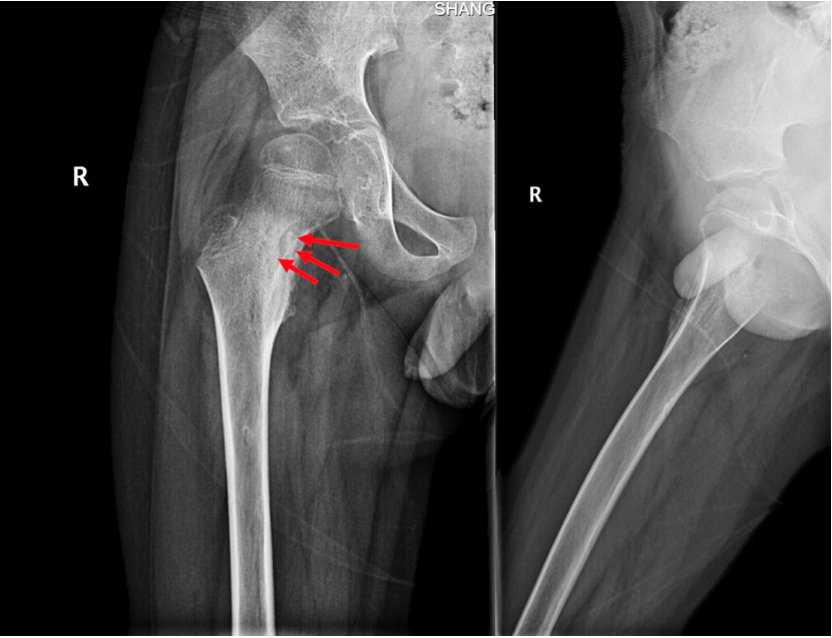

男性,20岁,因“左侧髋部疼痛不适一年余”就诊,一年前因入校军训后开始出现间歇性疼痛不适,夜间疼痛明显,口服止痛药物可以缓解,一年来逐渐加重,不敢患侧用力,不能进行体育活动,患者下肢出现肌肉萎缩。于外地多家医院就诊,行股骨X线、CT及MRI检查,诊断为“筋膜炎”、股骨骨岛、“骨样骨瘤可能”,无法确诊,患者日常生活困扰较大,后于我院就诊。

入院后诊断为中心型股骨髓腔骨样骨瘤,本型临床症状不如皮质型明显,部分患者疼痛隐匿,单纯射频消融效果较好。入院后第二天全身麻醉后导航下行左侧股骨病灶射频消融术,选择消融针尺寸为15毫米,消融时间11分30秒。术后第二天患者自诉原有疼痛不适症状缓解90%。术后复查MRI可见骨内明显的椭圆形消融范围,精准对应了23*19毫米的消融范围。

图1:股骨X线可见左侧股骨瘤巢形成及炎性成骨

图2:术前CT及MRI见髓腔内松质骨内的瘤巢及周围明显的成骨反应,MRI水肿反应不如骨膜及皮质骨型明显